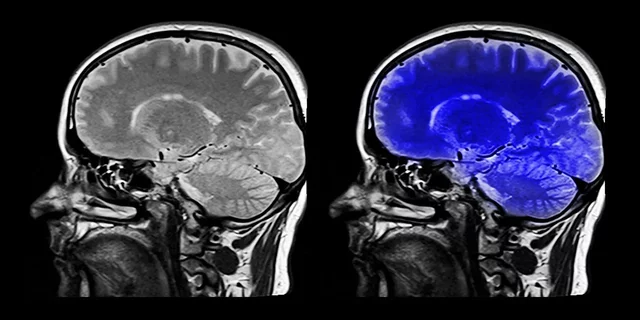

Surgen nuevas tecnologías que facilitan la forma de ver el funcionamiento cerebral, electroencefalograma, neuroimgenes, resonancias magnéticas, neurociencias y rehabilitación cognitiva.